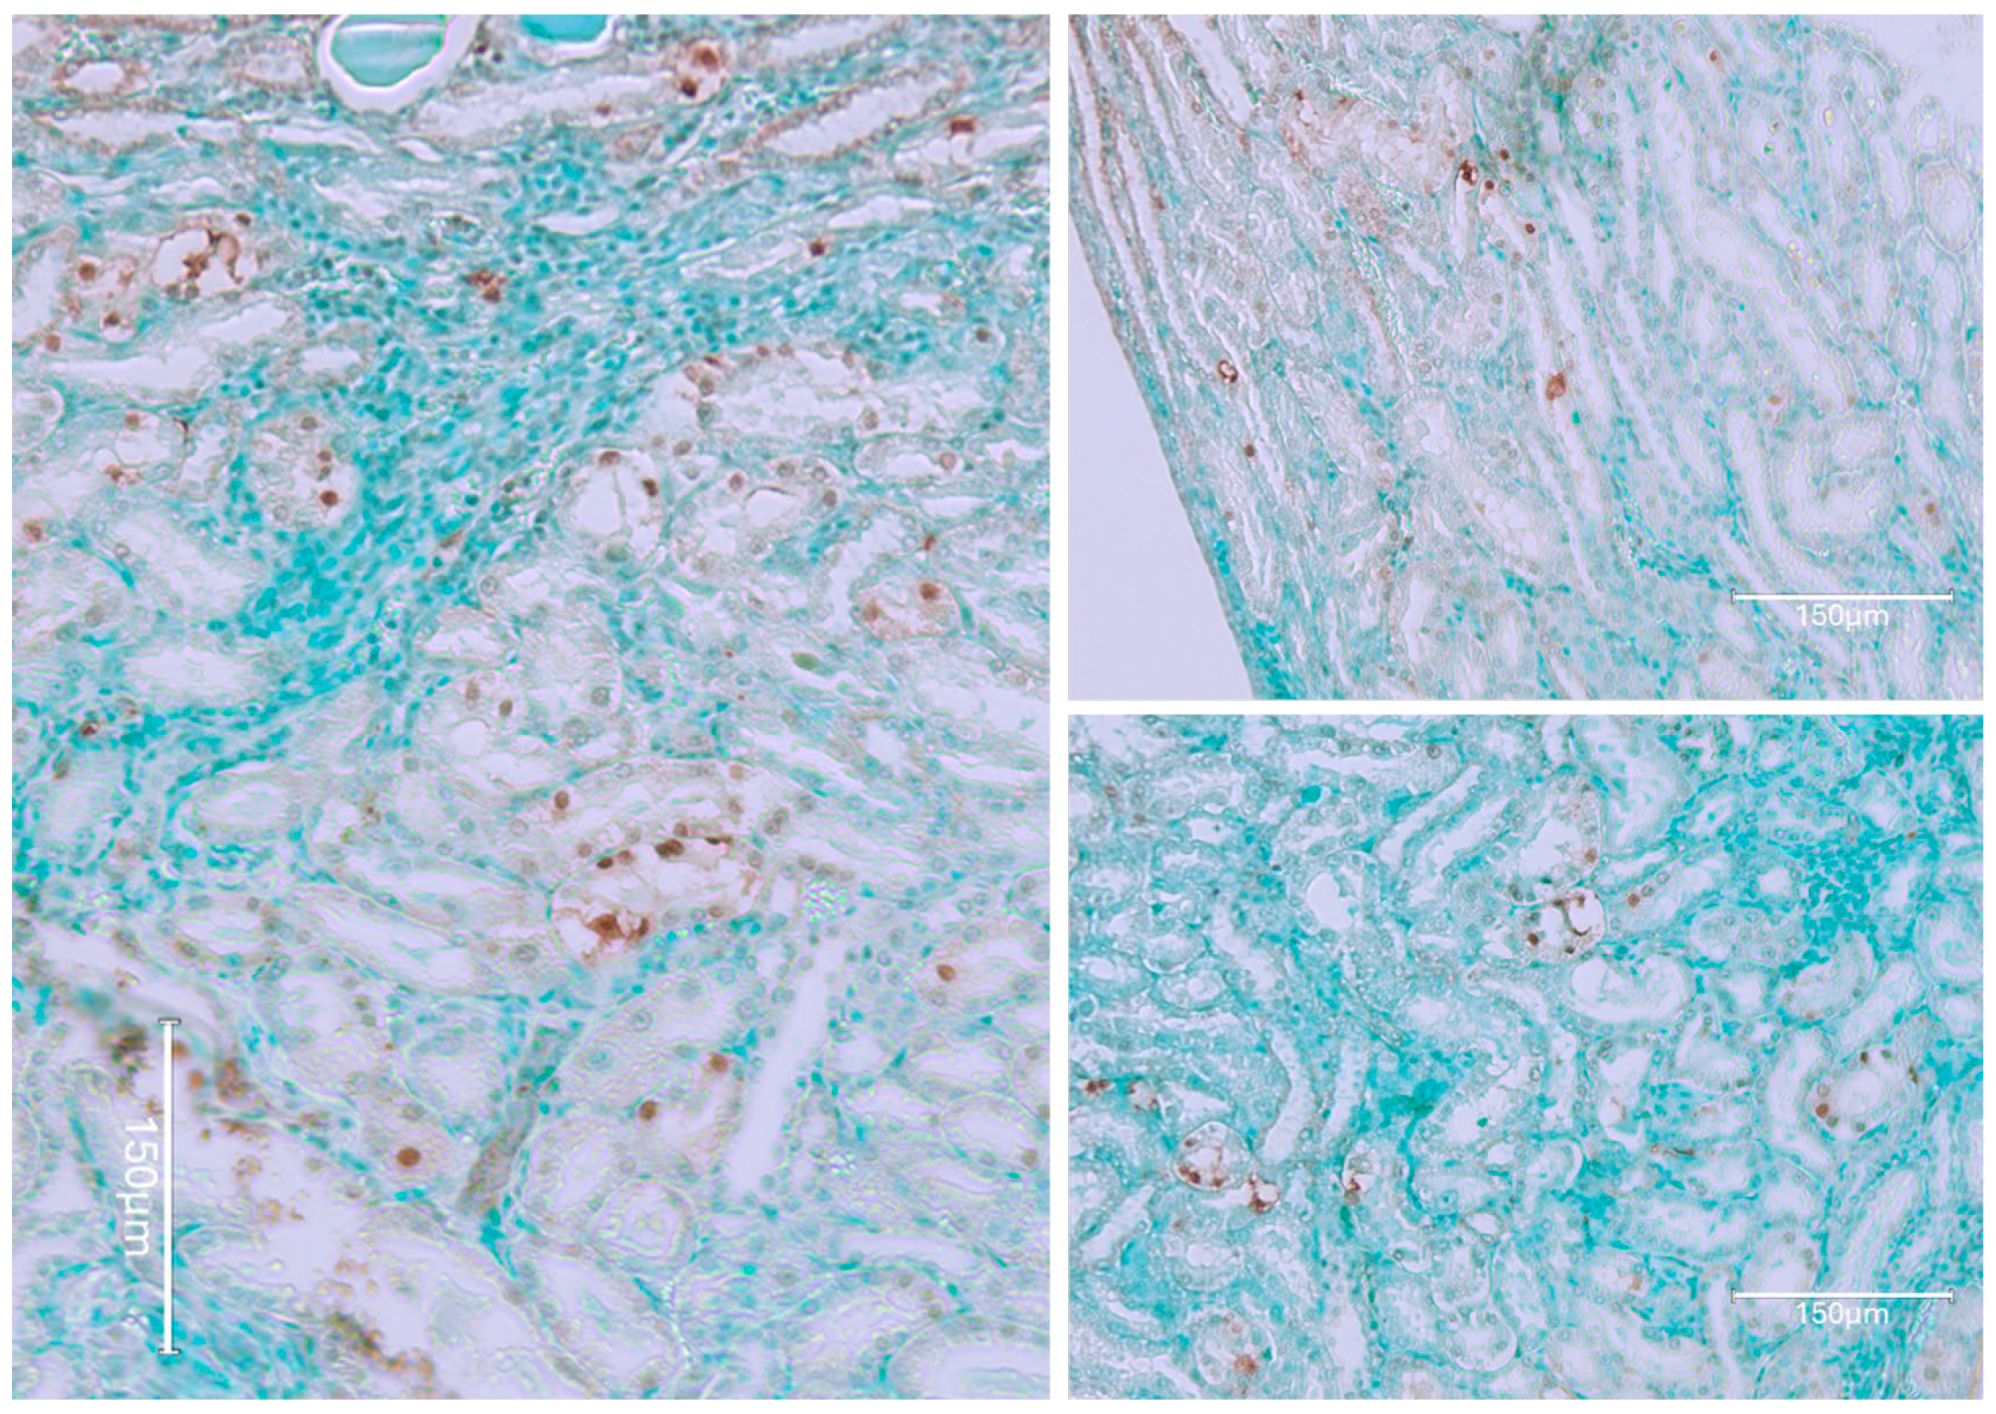

2.1. Carcinogenic Dose of Ochratoxin for Life for Three Fischer Rats

2.2. Low-Dose Ochratoxin for Life for Three Fischer Rats

2.3. Fischer Rat—Second Year OTA Only

2.4. Dark Agouti Rat—SINGLE RAT

- Miljkovic, A.; Mantle, P. Renal apoptosis in the mycotoxicology of Penicillium polonicum and ochratoxin in rats. Life 2022, 12, 352. [Google Scholar] [CrossRef]